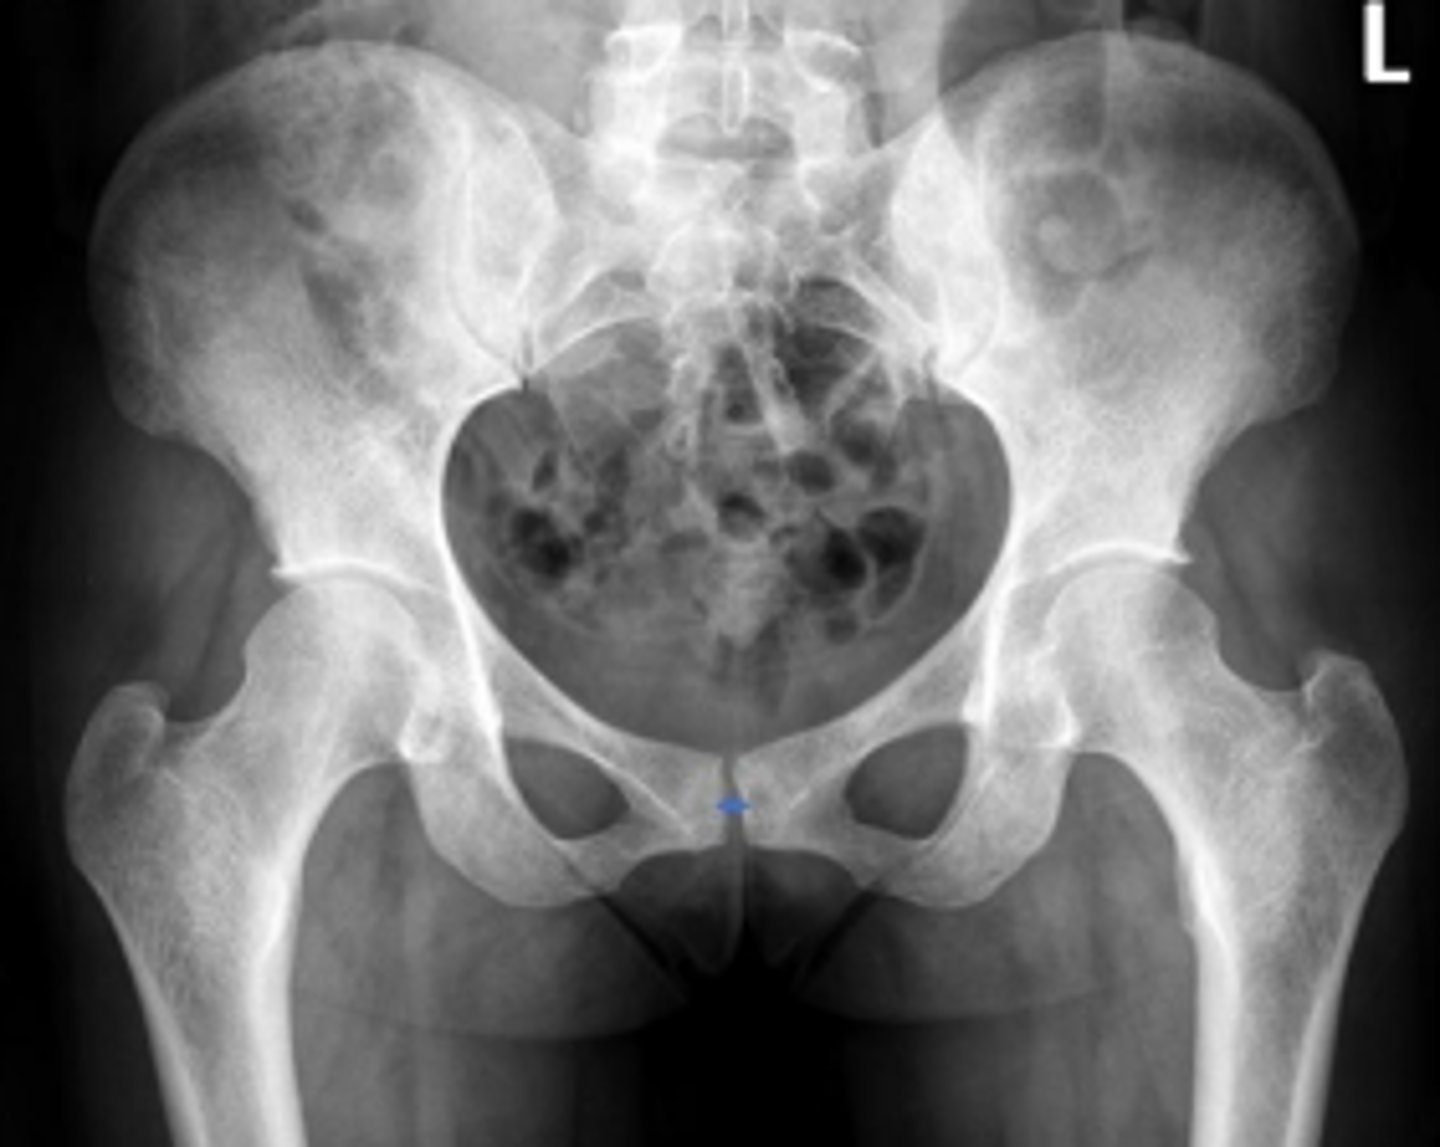

Bilateral frog leg view

What is the name of the radiographic view?

Phleboliths

What are the arrows pointing to?

Right ischial spine

Posterior rim of the right acetabulum

Anterior rim of the right acetabulum

Right sacroiliac joint space

What joint space is the arrow pointing to?

Lesser trochanter of the right femur

Greater trochanter of the right femur

Right posterior inferior iliac spine

Intertrochanteric line of the right femur

Right ischial tuberosity